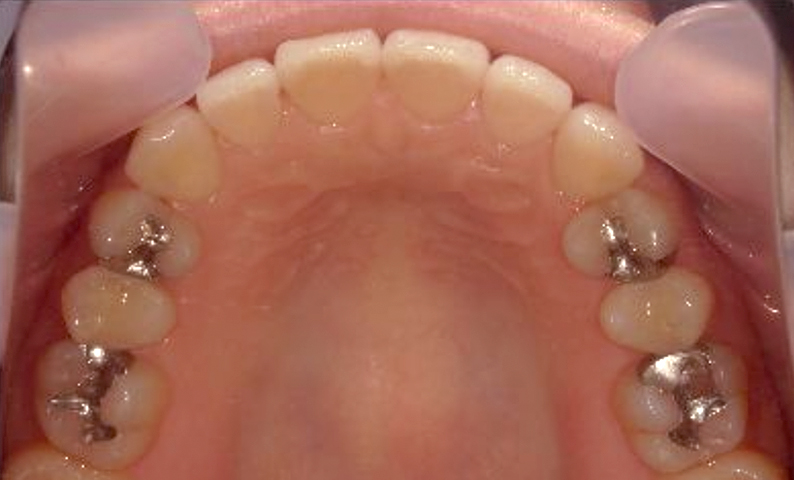

症例_003 下顎だけの部分矯正

治療期間:10ヶ月金額:24万円+税女性前歯のガタガタ下の前歯だけ上顎は補綴治療中

| Before | After |